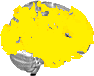

| Left Frontal Pole | 14 | 27% | 1881 |

| Left Insular Cortex | 15 | 60% | 692 |

| Left Superior Frontal Gyrus | 16 | 13% | 338 |

| Left Middle Frontal Gyrus | 17 | 12% | 316 |

| Left Inferior Frontal Gyrus, pars opercularis | 19 | 24% | 178 |

| Left Precentral Gyrus | 20 | 19% | 815 |

| Left Temporal Pole | 21 | 52% | 1219 |

| Left Superior Temporal Gyrus, anterior division | 22 | 54% | 136 |

| Left Superior Temporal Gyrus, posterior division | 23 | 56% | 490 |

| Left Middle Temporal Gyrus, anterior division | 24 | 50% | 222 |

| Left Middle Temporal Gyrus, posterior division | 25 | 61% | 775 |

| Left Middle Temporal Gyrus, temporooccipital part | 26 | 23% | 196 |

| Left Inferior Temporal Gyrus, posterior division | 28 | 34% | 335 |

| Left Inferior Temporal Gyrus, temporooccipital part | 29 | 21% | 149 |

| Left Postcentral Gyrus | 30 | 16% | 598 |

| Left Supramarginal Gyrus, anterior division | 32 | 32% | 306 |

| Left Supramarginal Gyrus, posterior division | 33 | 35% | 369 |

| Left Angular Gyrus | 34 | 43% | 409 |

| Left Lateral Occipital Cortex, superior division | 35 | 15% | 744 |

| Left Lateral Occipital Cortex, inferior division | 36 | 20% | 405 |

| Left Frontal Medial Cortex | 38 | 35% | 149 |

| Left Juxtapositional Lobule Cortex | 39 | 22% | 137 |

| Left Subcallosal Cortex | 40 | 14% | 71 |

| Left Paracingulate Gyrus | 41 | 54% | 724 |

| Left Cingulate Gyrus, anterior division | 42 | 27% | 272 |

| Left Cingulate Gyrus, posterior division | 43 | 15% | 148 |

| Left Frontal Orbital Cortex | 46 | 47% | 804 |

| Left Parahippocampal Gyrus, anterior division | 47 | 28% | 154 |

| Left Lingual Gyrus | 49 | 14% | 214 |

| Left Temporal Fusiform Cortex, anterior division | 50 | 18% | 57 |

| Left Temporal Fusiform Cortex, posterior division | 51 | 19% | 161 |

| Left Occipital Fusiform Gyrus | 53 | 22% | 197 |

| Left Frontal Operculum Cortex | 54 | 34% | 124 |

| Left Central Opercular Cortex | 55 | 55% | 542 |

| Left Parietal Operculum Cortex | 56 | 27% | 153 |

| Left Planum Polare | 57 | 56% | 202 |

| Left Heschl's Gyrus (includes H1 and H2) | 58 | 49% | 158 |

| Left Planum Temporale | 59 | 27% | 142 |

| Left Occipital Pole | 61 | 35% | 925 |

| Right Frontal Pole | 62 | 30% | 2494 |

| Right Insular Cortex | 63 | 51% | 602 |

| Right Superior Frontal Gyrus | 64 | 5% | 132 |

| Right Middle Frontal Gyrus | 65 | 29% | 752 |

| Right Inferior Frontal Gyrus, pars triangularis | 66 | 21% | 102 |

| Right Inferior Frontal Gyrus, pars opercularis | 67 | 40% | 262 |

| Right Precentral Gyrus | 68 | 6% | 243 |

| Right Temporal Pole | 69 | 43% | 1018 |

| Right Superior Temporal Gyrus, anterior division | 70 | 41% | 111 |

| Right Superior Temporal Gyrus, posterior division | 71 | 42% | 396 |

| Right Middle Temporal Gyrus, anterior division | 72 | 48% | 191 |

| Right Middle Temporal Gyrus, posterior division | 73 | 39% | 491 |

| Right Middle Temporal Gyrus, temporooccipital part | 74 | 37% | 428 |

| Right Inferior Temporal Gyrus, anterior division | 75 | 11% | 36 |

| Right Inferior Temporal Gyrus, posterior division | 76 | 20% | 193 |

| Right Inferior Temporal Gyrus, temporooccipital part | 77 | 19% | 148 |

| Right Superior Parietal Lobule | 79 | 12% | 174 |

| Right Supramarginal Gyrus, posterior division | 81 | 24% | 296 |

| Right Angular Gyrus | 82 | 43% | 628 |

| Right Lateral Occipital Cortex, superior division | 83 | 9% | 441 |

| Right Lateral Occipital Cortex, inferior division | 84 | 16% | 325 |

| Right Frontal Medial Cortex | 86 | 39% | 175 |

| Right Juxtapositional Lobule Cortex | 87 | 14% | 104 |

| Right Subcallosal Cortex | 88 | 36% | 176 |

| Right Paracingulate Gyrus | 89 | 59% | 812 |

| Right Cingulate Gyrus, anterior division | 90 | 43% | 544 |

| Right Cingulate Gyrus, posterior division | 91 | 15% | 174 |

| Right Frontal Orbital Cortex | 94 | 45% | 655 |

| Right Parahippocampal Gyrus, anterior division | 95 | 12% | 77 |

| Right Lingual Gyrus | 97 | 5% | 83 |

| Right Temporal Fusiform Cortex, anterior division | 98 | 15% | 45 |

| Right Temporal Fusiform Cortex, posterior division | 99 | 23% | 162 |

| Right Temporal Occipital Fusiform Cortex | 100 | 12% | 99 |

| Right Occipital Fusiform Gyrus | 101 | 27% | 237 |

| Right Frontal Operculum Cortex | 102 | 45% | 147 |

| Right Central Opercular Cortex | 103 | 48% | 434 |

| Right Parietal Operculum Cortex | 104 | 38% | 204 |

| Right Planum Polare | 105 | 56% | 217 |

| Right Heschl's Gyrus (includes H1 and H2) | 106 | 71% | 201 |

| Right Planum Temporale | 107 | 54% | 224 |

| Right Occipital Pole | 109 | 34% | 856 |